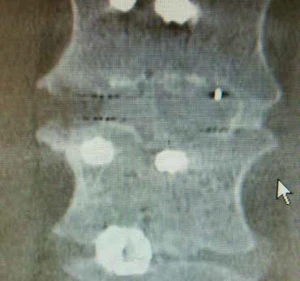

Spine & Orthopaedics

Invibio provides PEEK-OPTIMA™ polymers for implants that restore mobility and support bone integration in spinal and joint procedures. These materials combine mechanical strength with radiolucency for precise surgical assessment.